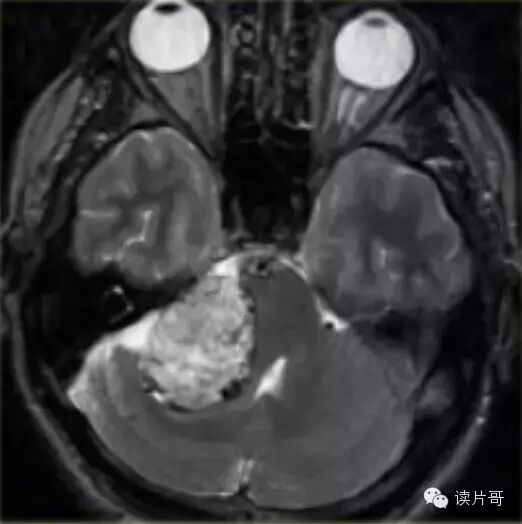

顱內黑色素瘤-小腦黑色素瘤1例

導讀:顱內黑色素瘤常發生於中年人或老年人,分為原發性和轉移性,原發性黑色素細胞瘤為顱內極為罕見的腫瘤,約占顱內腫瘤的0.07...

橋腦小腦角黑色素瘤1例

顱內黑色素瘤常發生於中年人或老年人,分為原發性和轉移性,原發性黑色素細胞瘤為顱內極為罕見的腫瘤,約占顱內腫瘤的0.07%~0.17%...